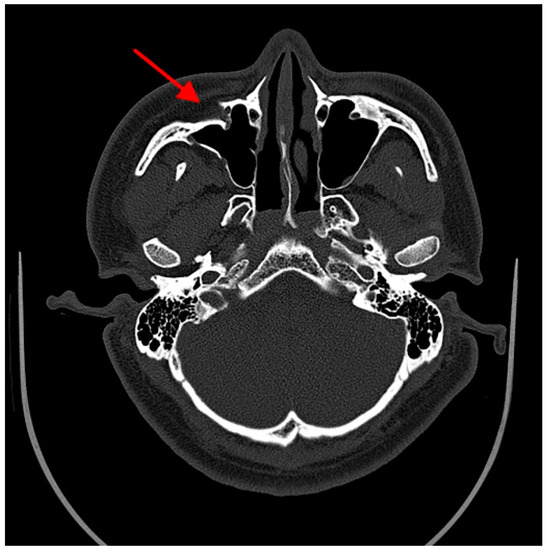

3. Results

4. Discussion